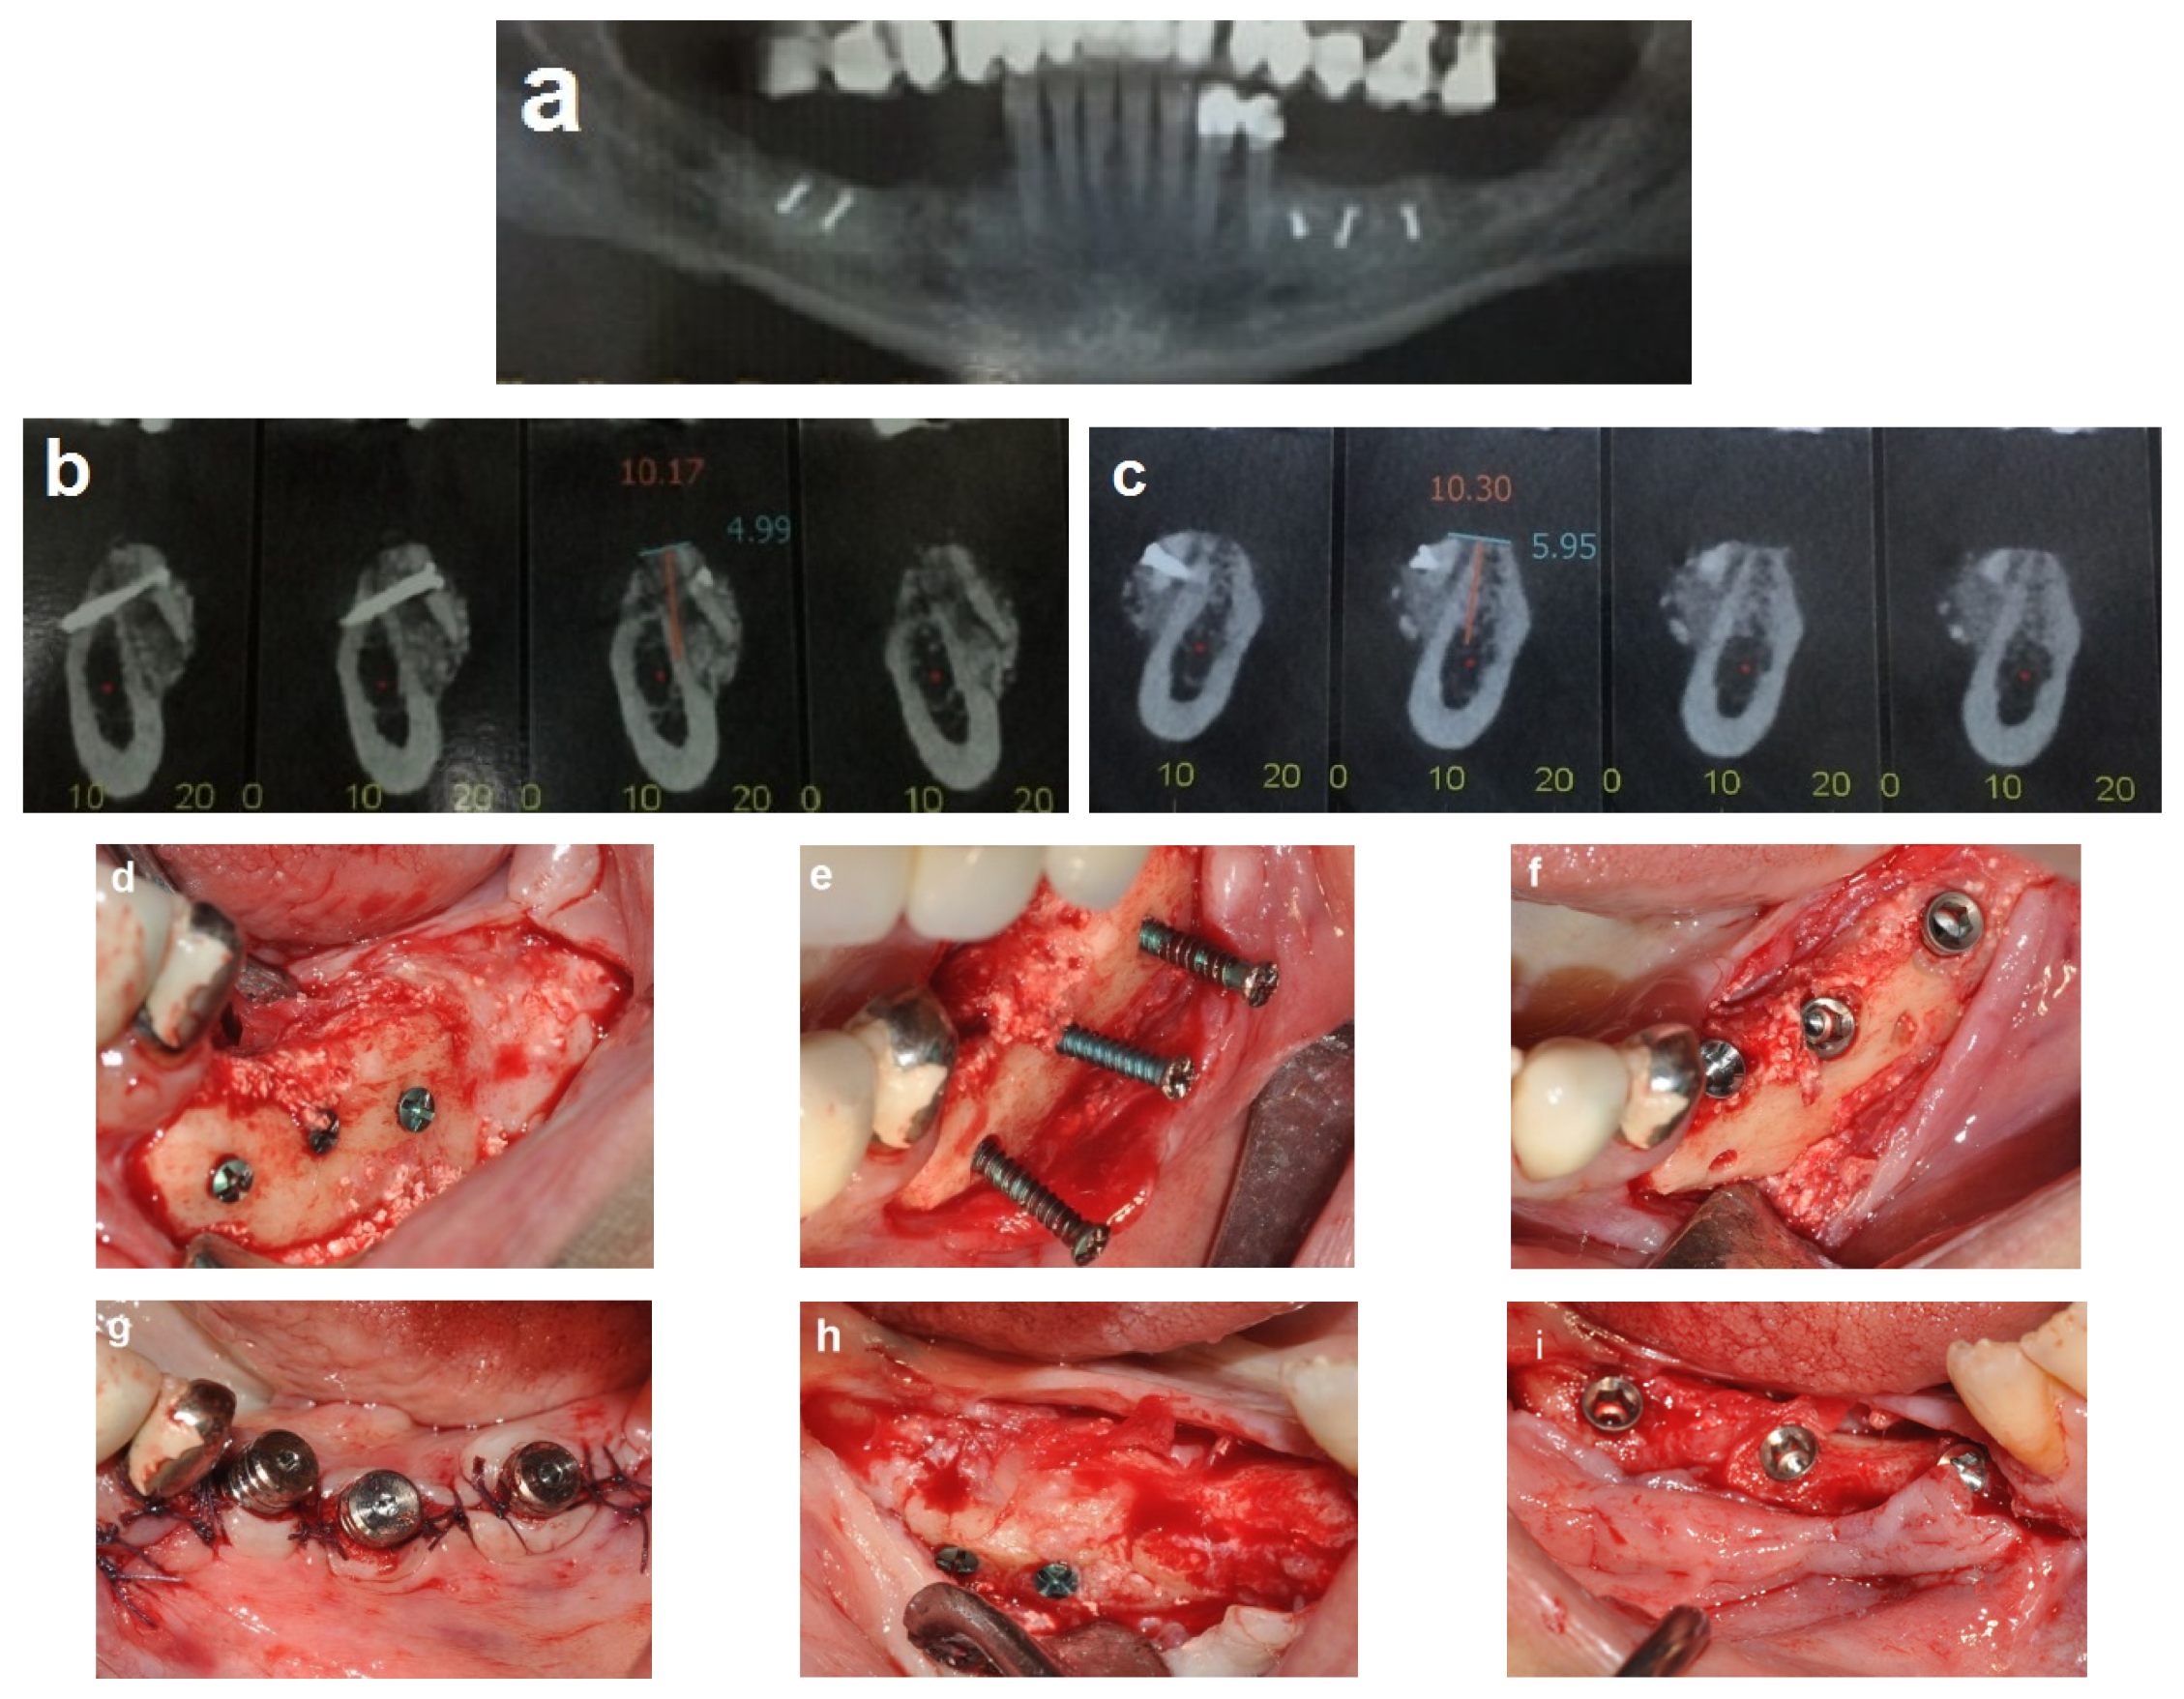

Follow-up was scheduled three times every two weeks, then monthly. Partial exposure of the graft occurred at four weeks on the right side but was successfully managed without compromising the augmentation outcome. A CBCT scan was obtained after four months to assess the bone gain (Figure 4a–c). Dental implants were placed 4 months after the procedure (Figure 4d–i). A fixed prosthesis was delivered four months after the implant placement. This case was followed for 10 years (Figure 5).

Figure 4.

Reentry at 4 months. (a–c) CBCT post-op demonstrating significant horizontal bone gain. (d) Left-side view, showing excellent integration of the bone blocks and the width of the new bone demonstrated by the length of the removed fixation screws (e). (f,g) Placement of three implants on the left side. (h) New bone volume on the right side. (i) Placement of three implants on the right side.